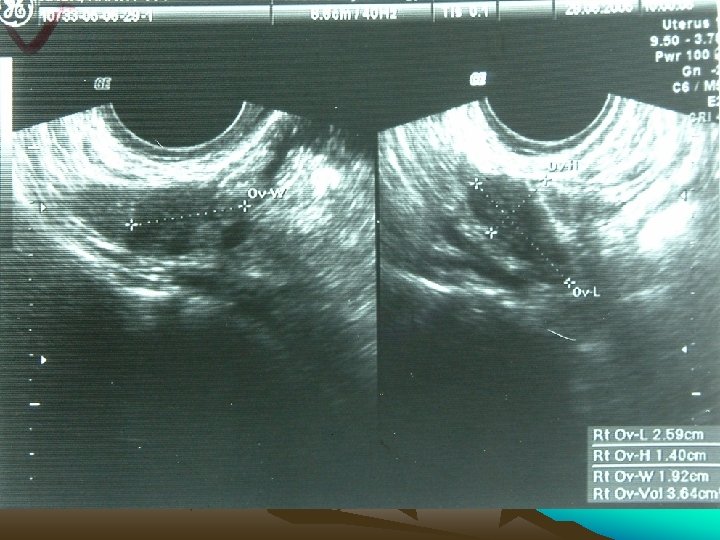

H: • 59 y , Postmenopausal, Dysphagia, & bleeding p/v, (year 2005 at AIIMS) • ANA +, Arthritis, Malar pigmentation • Ca ® Breast p. T 2 N 0 M 0 (July ‘ 02) • BCS • Breast RT + electron boost • Adjuvant CMF 6# • ER, PR & HER 2 -neu + • Tamoxifen 20 mg OD 2

Investigations • • • Chest X Ray USG CECT EUS Ba Swallow 3

Present Complaints • Bleeding P/V x 2 months (July 2005) • Hematemesis, Wt loss • GPE N

H: • • 59 y , Postmenopausal Ca ® Breast p. T 2 N 0 M 0 (July ‘ 02) BCS Breast RT + electron boost Adjuvant CMF 6# ER, PR & HER 2 -neu + Tamoxifen 20 mg OD

Bleeding PV • All causes + • Tamoxifen induced hyperplasia, polyp, carcinoma, • Mets from Metastatic Lobular breast CA